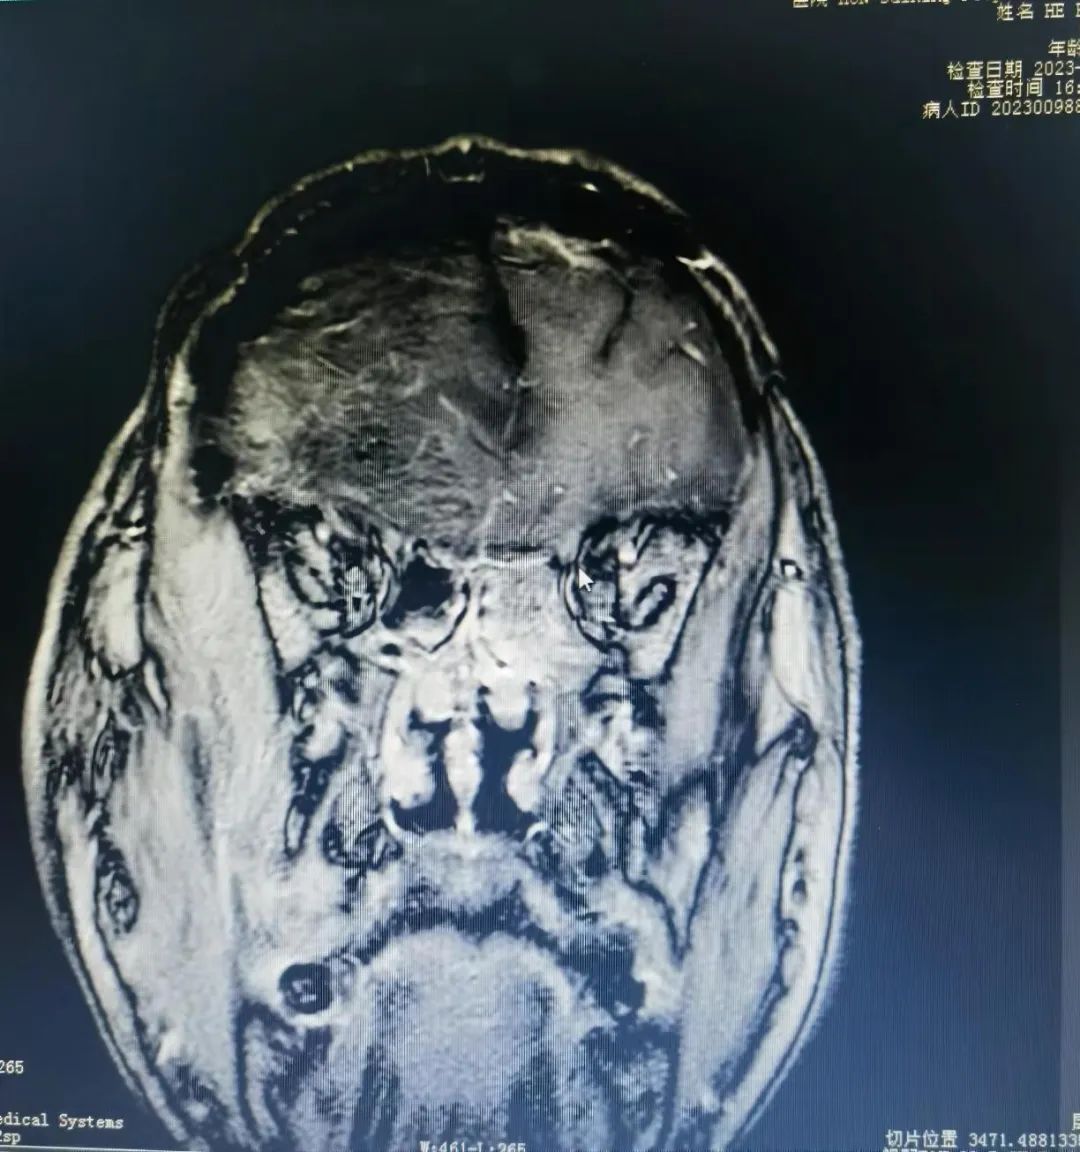

66岁的贺大爷(化名)平时下地干活特别麻利,也特别注重身体锻炼,自觉身体很棒,很少进行健康体检。七月中旬,贺大爷起床后发现眼睛视物不清,偶尔还有头痛、头昏的症状,家属见状立即将其送到绥宁县人民医院就诊检查。门诊CT检查提示右侧额部占位病变,考虑脑膜瘤可能性大,随即入住神经外科,并经中南大学湘雅医院驻绥专家廖新斌博士及县人民医院神经外科主任黄敏认真仔细讨论、会诊后,诊断为右侧巨大脑膜瘤,需进行手术切除。 当听到专家说是颅内肿瘤时,贺大爷顿时愣住了,家属也更加着急起来。廖新斌博士和黄敏主任立即安抚道:“脑膜瘤是颅内常见肿瘤,也是中枢神经系统最常见的原发性肿瘤,多为良性,生长缓慢且隐匿,手术切除肿瘤后均能取得很好的恢复效果,神经功能也能很快恢复。”并耐心为其说明手术治疗的优势和相关事项,对他们提出的各种疑问给予了细致的解答,最大程度地打消了贺大爷及家属对手术的顾虑,最终选择手术治疗。

术前VS术后

术前VS术后 在廖新斌博士和黄敏主任的带领下,神经外科团队认真讨论并充分做好术前准备,如期为贺大爷实施了“前颅窝底复发肿瘤”切除术。手术效果及术后恢复良好,贺大爷于8月3日康复出院,并对科室团队的专业技术和卓越服务竖起了大拇指,其家属也送来锦旗表示感谢。